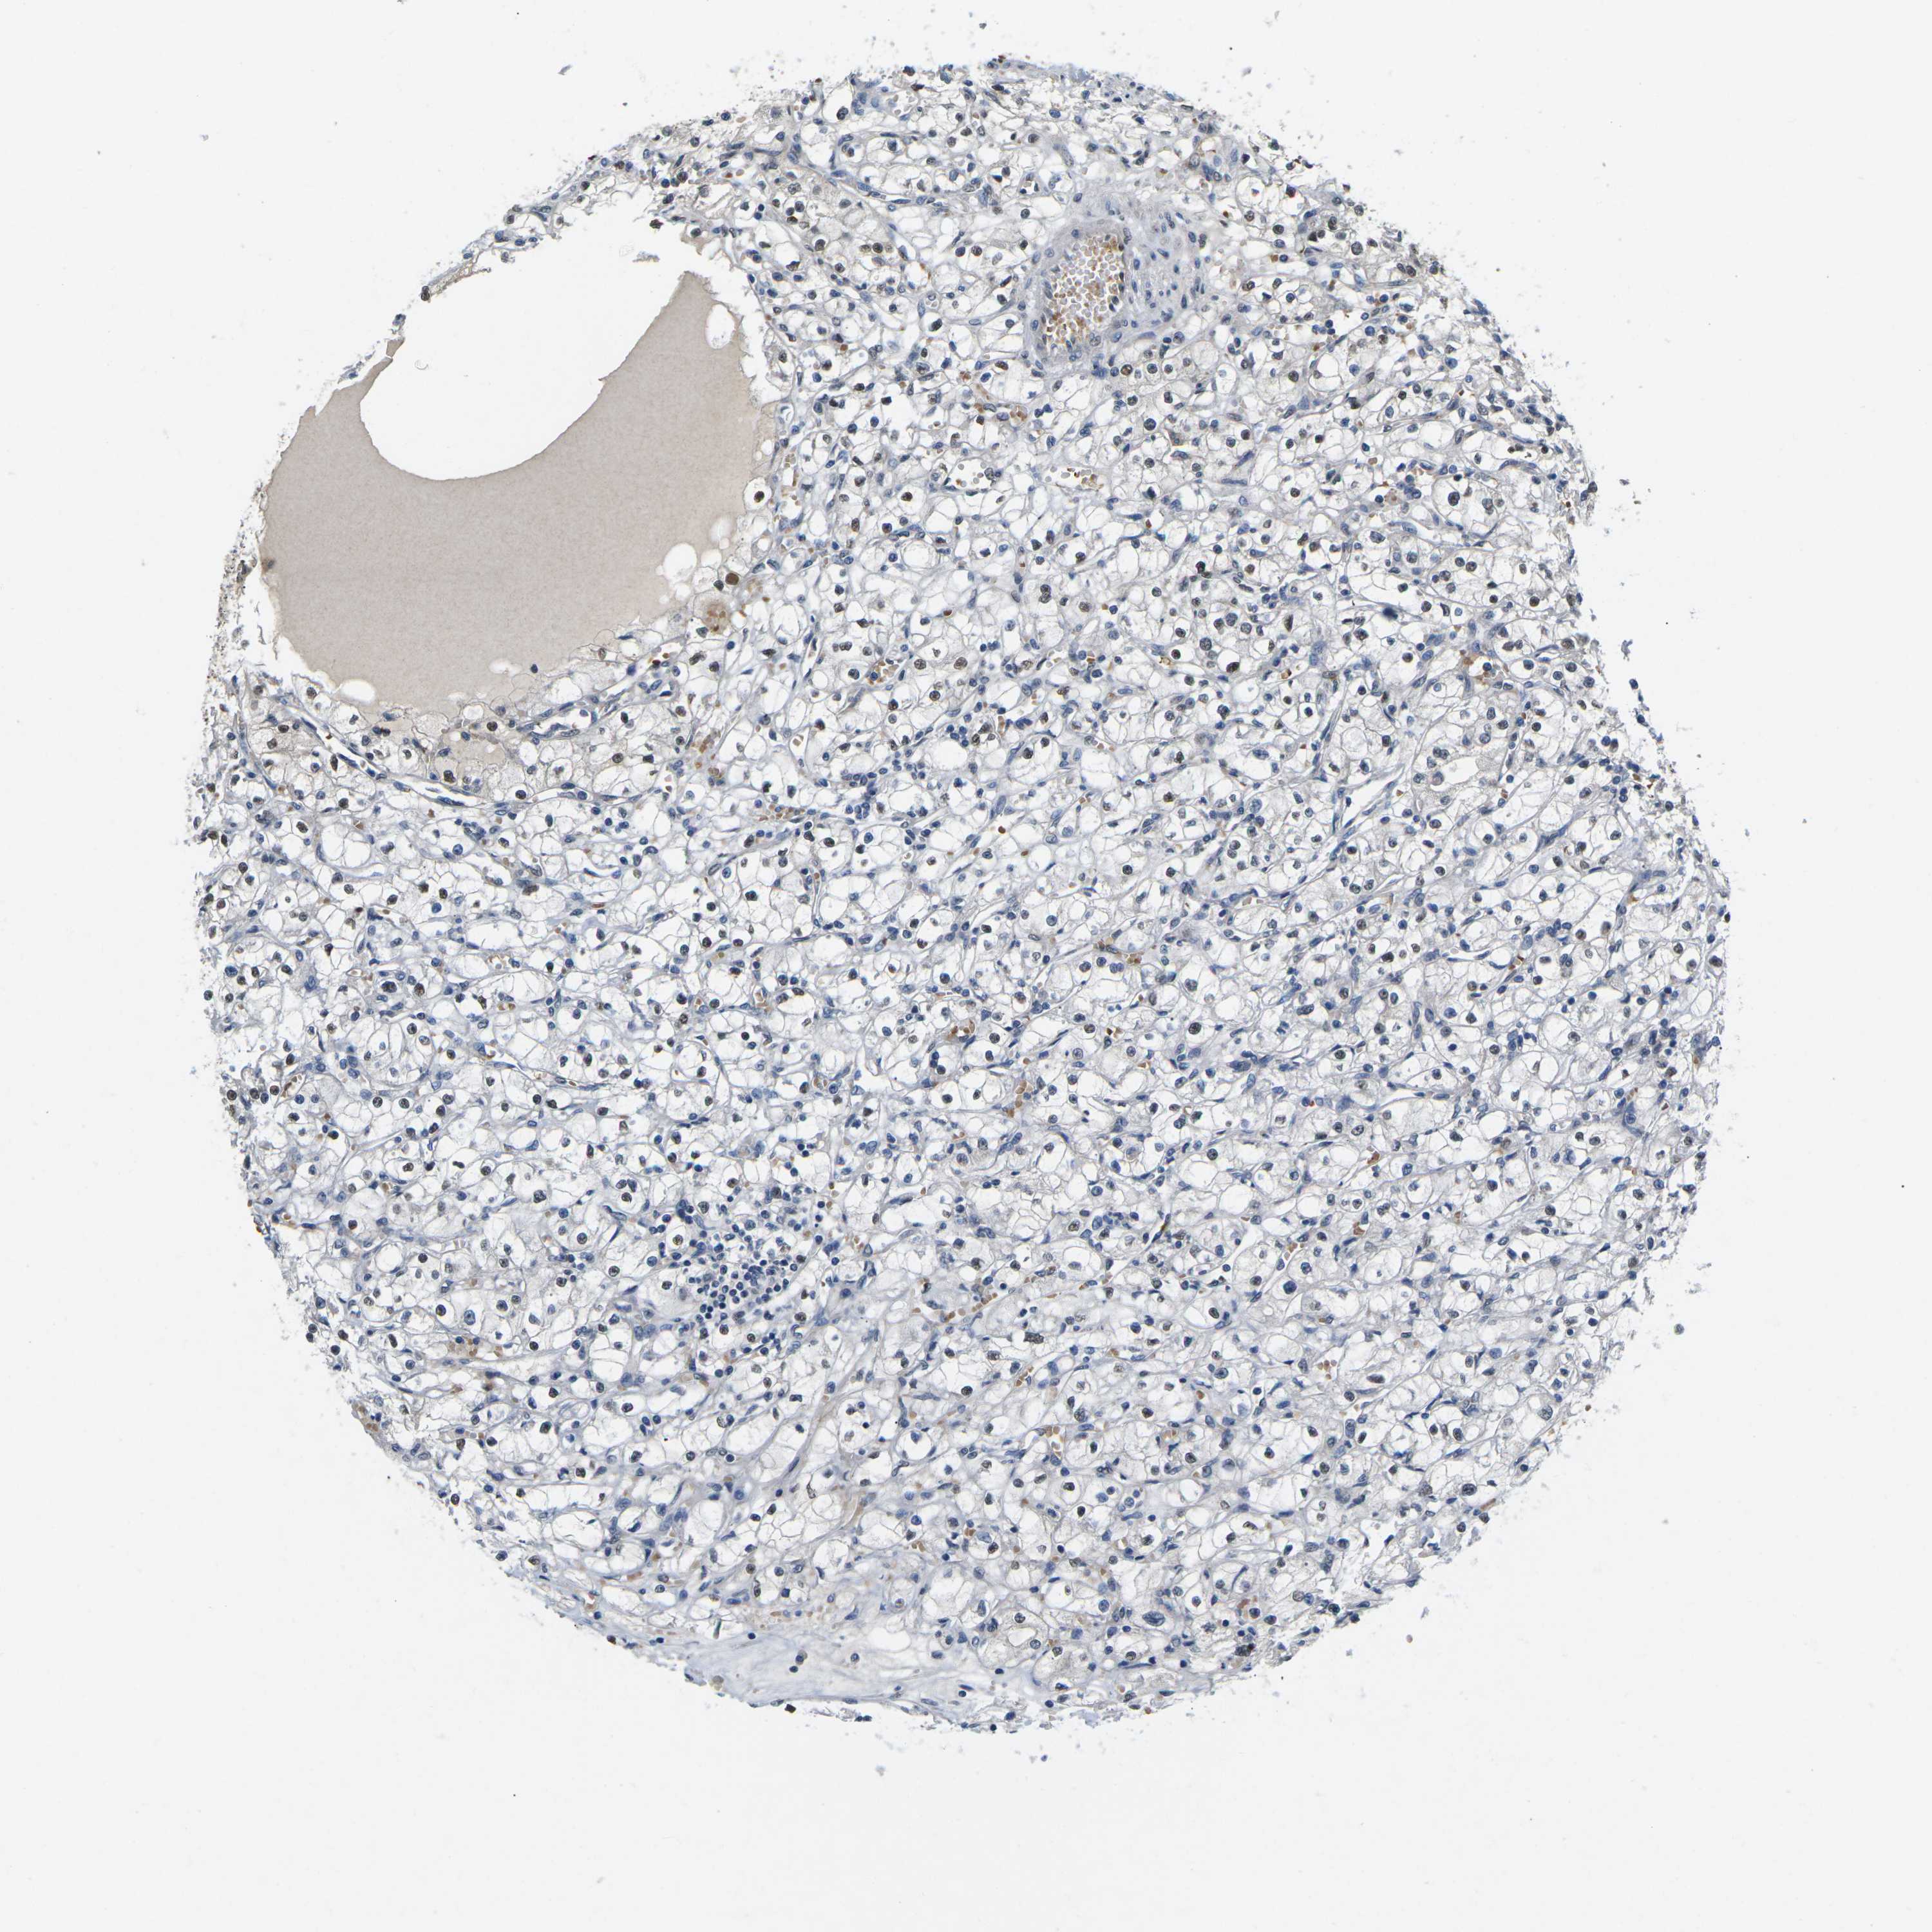

TCGA RNA samplesi

RNA-seq data is reported as average FPKM (number Fragments Per Kilobase of exon per Million reads), generated by the The Cancer Genome Atlas (TCGA) .

Normal distribution across the dataset is visualized with box plots, shown as median and 25th and 75th percentiles. Points are displayed as outliers if they are above or below 1.5 times the interquartile range. FPKM values of the individual samples are presented next to the box plot.

Average pTPM 0.2

Number of samples 100